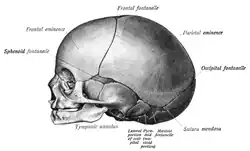

At birth, the human skull is made up of 44 separate bony elements. During development, many of these bony elements gradually fuse together into solid bone (for example, the frontal bone). The bones of the roof of the skull are initially separated by regions of dense connective tissue called fontanelles. There are six fontanelles: one anterior (or frontal), one posterior (or occipital), two sphenoid (or anterolateral), and two mastoid (or posterolateral). At birth, these regions are fibrous and moveable, necessary for birth and later growth. This growth can put a large amount of tension on the "obstetrical hinge", which is where the squamous and lateral parts of the occipital bone meet. A possible complication of this tension is rupture of the great cerebral vein. As growth and ossification progress, the connective tissue of the fontanelles is invaded and replaced by bone creating sutures. The five sutures are the two squamous sutures, one coronal, one lambdoid, and one sagittal suture. The posterior fontanelle usually closes by eight weeks, but the anterior fontanel can remain open up to eighteen months. The anterior fontanelle is located at the junction of the frontal and parietal bones; it is a "soft spot" on a baby's forehead. Careful observation will show that you can count a baby's heart rate by observing the pulse pulsing softly through the anterior fontanelle.

The skull in the neonate is large in proportion to other parts of the body. The facial skeleton is one seventh of the size of the calvaria. (In the adult it is half the size). The base of the skull is short and narrow, though the inner ear is almost adult size.[15]